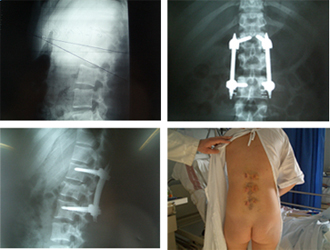

Técnicas 3

Imágenes de una artrodesis vertebral por técnica mínimanente invasiva donde puede apreciarse el abordaje de la zona intersomática para la colocación de espaciadores con injerto y de la instrumentación posterior.

Técnicas 4Escoliosis tratada por técnica mínimamente invasiva con imágenes radiográficas y de las cicatrices a los dos años de la intervención.